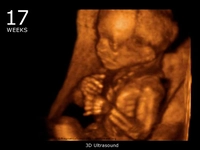

• 17. Hafta: Fetüs, işitme yeteneği kazanır. Anne adayı, karnındaki hareketleri hissedebilir.